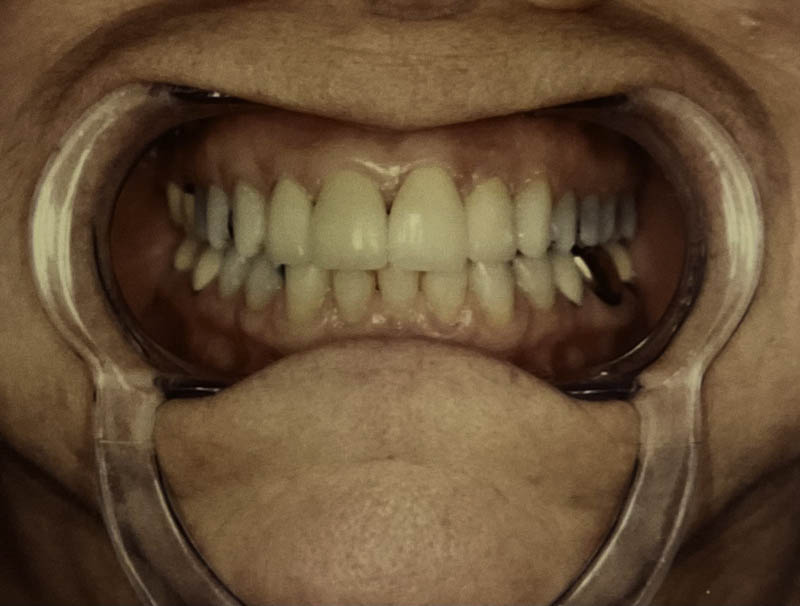

Before

After

Invisalign® Clear Aligners

Case Highlight